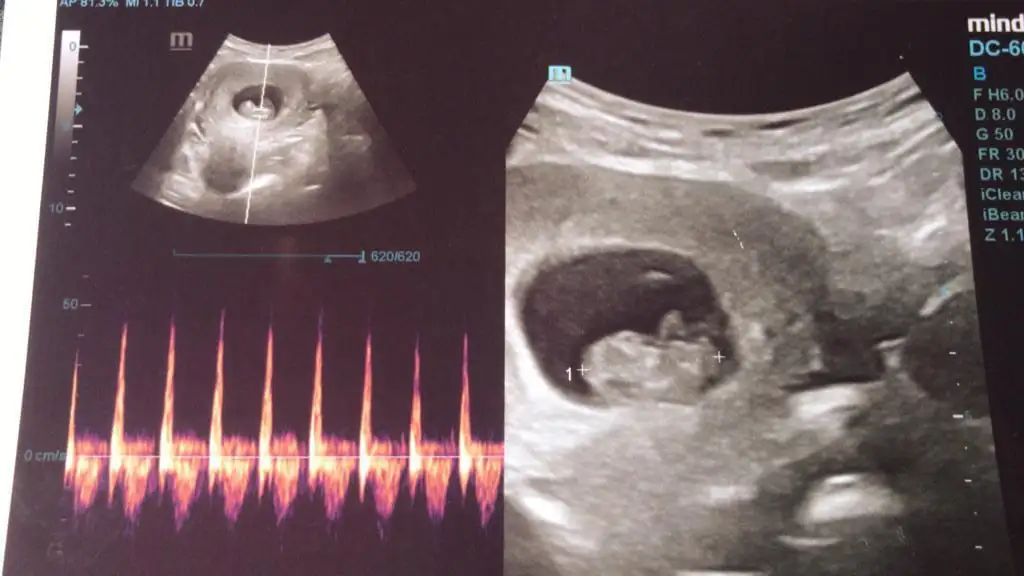

Banada tahminde bulunurmusunuz acaba,biri 6 haftalik digeri 9 haftalik,

DF51552A-B482-4254-81FB-8960F95AA8DE.webp

simdiden tesekkürler